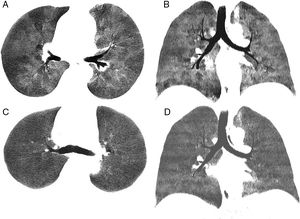

We report the case of a 39-year-old man with a history of Stage IV diffuse large B-cell lymphoma treated with several lines of chemotherapy who, after achieving complete remission, underwent HSCT from a matched donor in April 2015. Ten months after the procedure, the patient developed GVHD with cutaneous, gastrointestinal and pulmonary manifestations that did not respond favorably to treatment with corticosteroids and extracorporeal photopheresis. Lung function tests prior to developing GVHD were normal, but subsequently showed an obstructive pattern of moderate intensity, with forced expiratory volume in 1 second (FEV1) 59% predicted value, forced vital capacity (FVC) 78%, and FEV1/FVC 68%, along with a 71% decrease in CO diffusion capacity from pre-GVHD values. Dynamic computed tomography (dCT) of the chest in inspiration and expiration showed extensive areas of air trapping in both lungs (Fig. 1A and B), while infectious complications were ruled out. Bronchoalveolar lavage revealed no opportunistic infections. Given these findings, a diagnosis of BO refractory to corticosteroids and extracorporeal photopheresis associated with post-HSCT GVHD was given. The patient received ruxolitinib and achieved progressive improvement of the GVHD manifestations, including BO. Four months after starting ruxolitinib, lung function tests showed significant improvement, with an increase in FEV1 (72%), FVC (80%), and FEV1/FVC (71%), although mild air trapping persisted on plethysmography, with a residual volume of 128% and residual volume/total lung capacity ratio of 127%. Reduced signs of air trapping in the expiratory phase were also observed on dCT 3 months after starting ruxolitinib (Fig. 1C and D).

Chest minIP (Minimum Intensity Projection) CT axial (A) and coronal (B) images in expiration showing a marked mosaic attenuation pattern in the pulmonary parenchyma, with geographical regions of low density alternating with areas of greater attenuation. The areas of lower density correspond to air trapping. Chest minIP (Minimum Intensity Projection) CT axial (C) and coronal (D) images in expiration showing less heterogeneity and greater uniformity of the attenuation of the pulmonary parenchyma with compared to images (A) and (B).